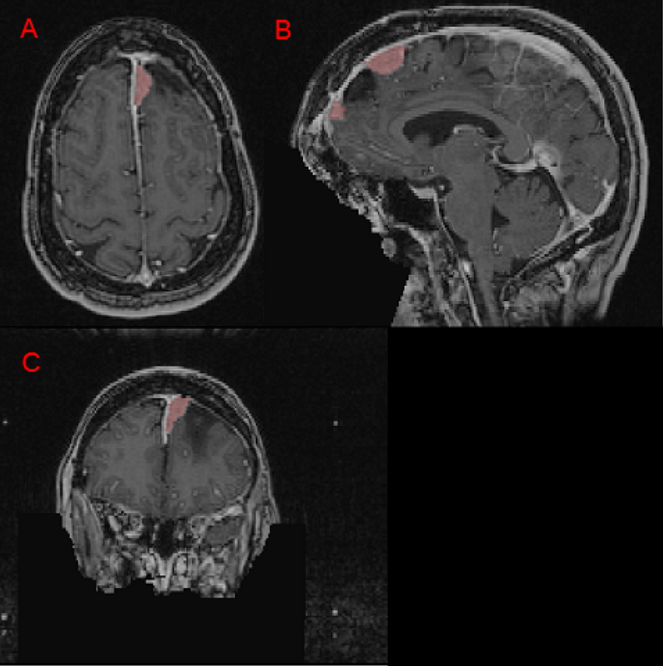

All visible intracranial meningiomas are included in the GTV label, even if they were not treated in the real world clinical scenario (Figure 4). The rationale for labeling all meningioma is to allow the treating radiation oncology team the opportunity to utilize automated segmentations for any and all meningioma within the patient’s respective brain MRI. This approach also ensures that automated segmentation algorithm training will not be adversely affected by non-segmented non-target meningiomas.

Refer to caption

Figure 4: Panels A, B, and C depict an anterior left falx meningioma (red) on axial, sagittal, and coronal images respectively. Panel B demonstrates an area of hypointense edema between two separate anterior falcine meningiomas. Note that the hypointense edema region is not labeled since this is not typically treated in meningioma radiotherapy. Panel C shows a coronal slice demonstrating the distinct intensity difference between the zero T1c intensity, true black, defaced region (blue arrow) compared to the low T1c intensity, gray, region outside the patient’s head (green arrow).